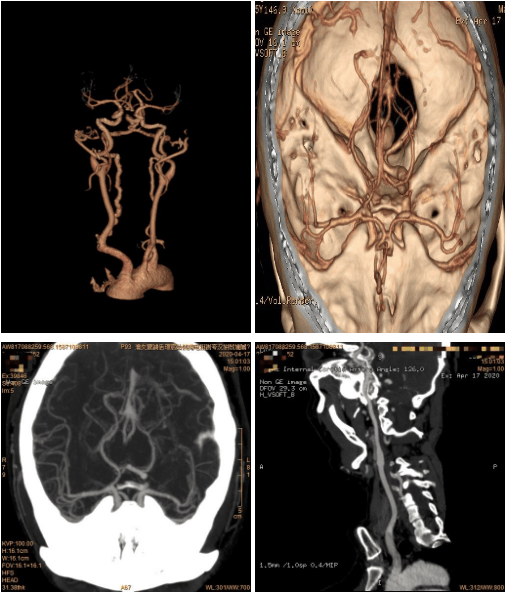

利用CT增强阈值触发式扫描及图形后处理功能检查头颈部血管图像

1.颅脑:脑肿瘤、脑血管病变、颅内感染性病变和先天变异等。

4.头颈部血管瘤,血管狭窄等疾病,胸腹主动脉(夹层、动脉瘤、脉管炎),肾脏CTU等。